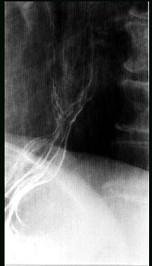

问题 女性,65岁,进行性吞咽困难半年,消瘦,钡餐检查如图,最佳的诊断是 ( )

选项 A.贲门失弛缓症 B.食管静脉曲张 C.食管鳞状(上皮)细胞癌 D.贲门癌 E.反流性食管炎

答案 C